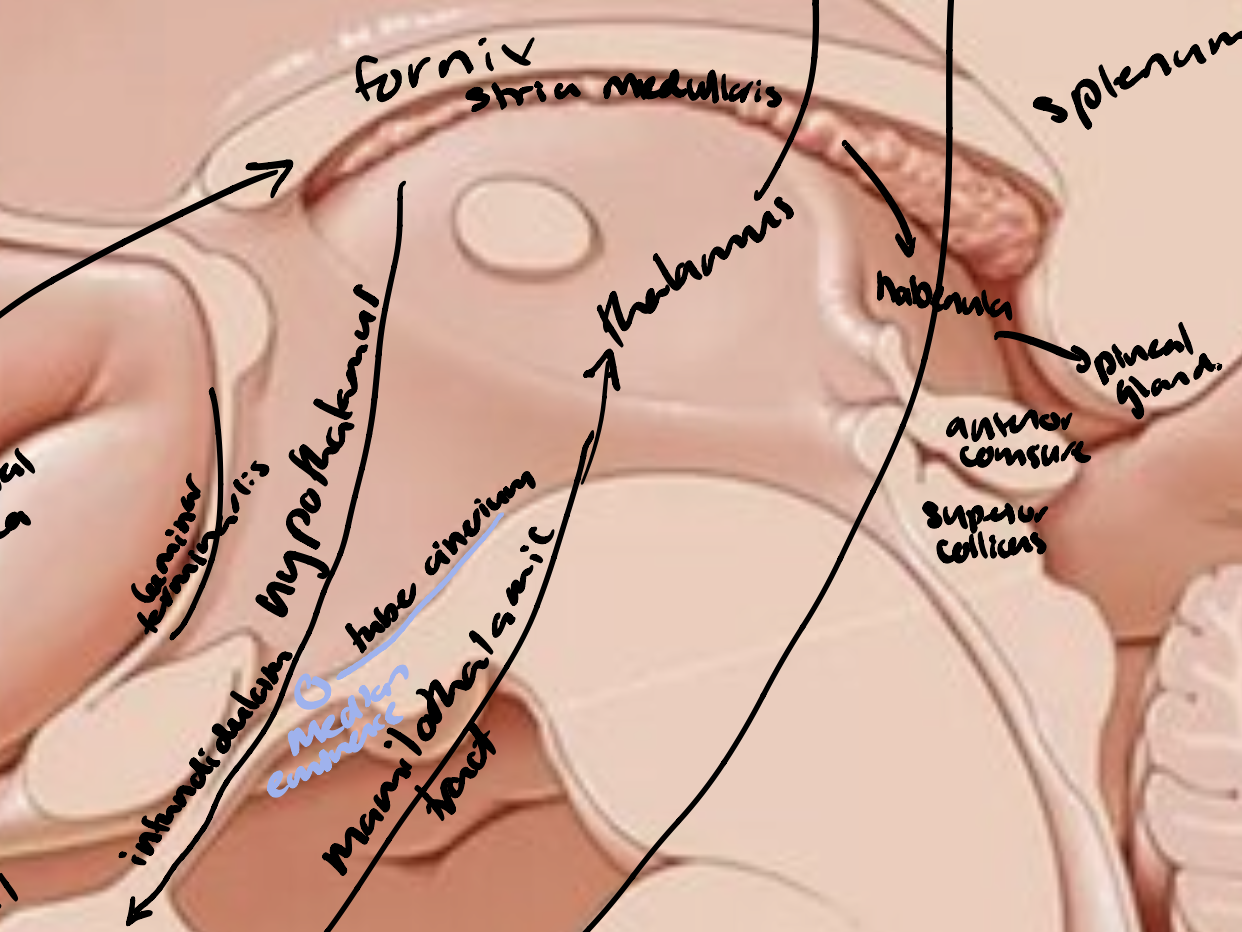

Diencepathon

Thalamus

Interthalamic mass

Striae medullaris thalami

Habenular nucleus

Pineal gland

Hypothalamus

The limbic lobe

Fornix

Mammillothalamic tract

Stria medullaris thalami

The Papez Circuit

Parahippocampal gyrus → hippocampus → fimbriae → fornix → mammillary bodies (hypothalamus) → mammillothalamic tract → nuclei of thalamus → cingulate gyrus → parahippocampal gyrus/entorhinal cortex

Hypothalamus

Anterior commissure

Lamina terminalis

Thalamus

Optic chiasm

Infundibulum and pituitary gland

Tuber cinereum

Mammillary bodies

Cingulate gyrus

Fornix

Striae medullaris thalami

Pineal gland

Posterior commissure